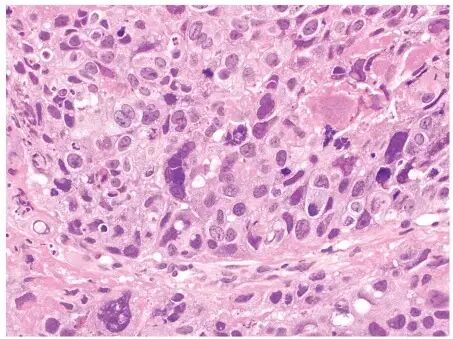

胃食管交界处活检病理显示伴有异性中间体和滋胚层的低分化浸润癌暗示绒毛膜癌。免疫组化染色显示,肌酸激酶 7(见于腺癌和上皮性肿瘤)、 SALL4/PLAP(生殖细胞标记物)和β-hCG 阳性,抑制素(见于卵泡颗粒细胞瘤)、CK20/CDX2(见于胃腺癌)和 OCT4(未分化细胞标记物)弱阳性或局部染色。

注:胃绒毛膜癌(苏木精伊红染色)